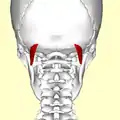

Position du muscle oblique supérieur de la tête (en rouge).

Position du muscle oblique supérieur de la tête (en rouge). Le muscle oblique supérieur de la tête. Vue postérieure.